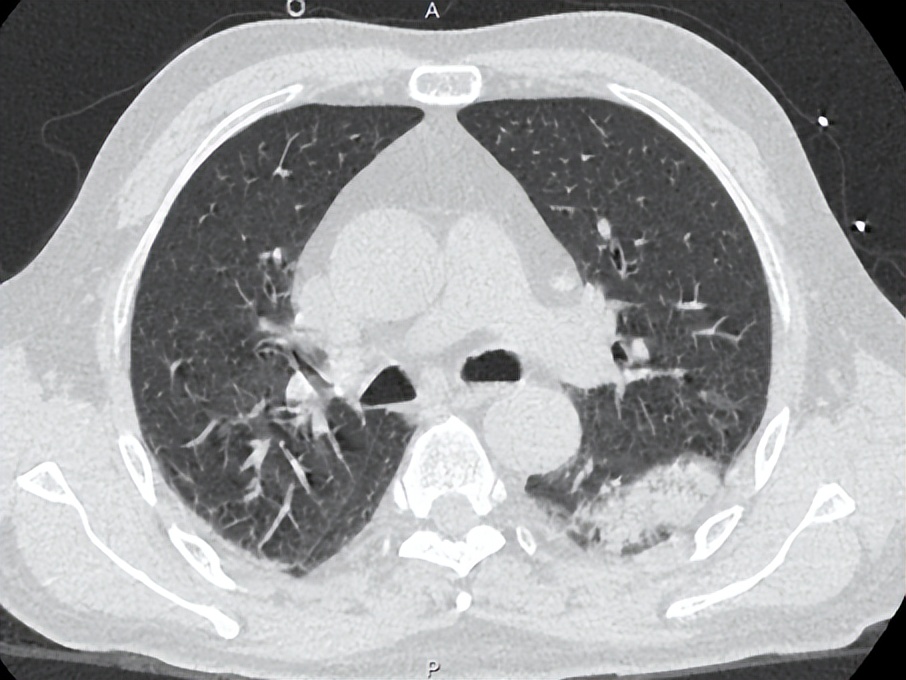

胸部CT平扫,颅脑CT平扫:1. 左肺下叶炎症 。2.右肺下叶胸膜下区条片灶,考虑肺通气不良所致。3.纵隔多发稍大淋巴结,左肺门散在钙化淋巴结。4.胸4、胸7椎体骨岛可能。5.脂肪肝。6.左侧基底节区小软化灶可能;桥脑左侧份条状稍低密度,拟伪影干扰。7.左侧额骨局部骨质不连,请结合病史。8.副鼻窦少许炎症。

治疗后患者湿罗音减少,左肺可闻及Velcro啰音,7-6复查胸部CT如下: